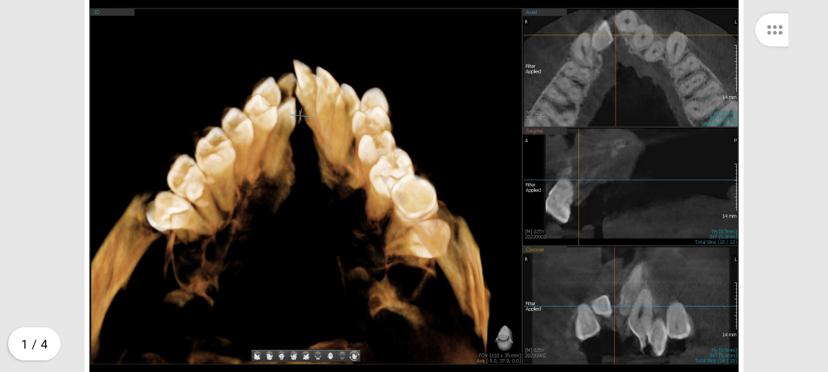

Implantology

Enhances dental implant planning by offering a detailed view of bone density, structure, and anatomical landmarks, ensuring accurate and safe implant placement.

Orthodontics

Provides comprehensive 3D imaging to evaluate jaw alignment, tooth position, and growth patterns, aiding in more precise orthodontic treatment planning.